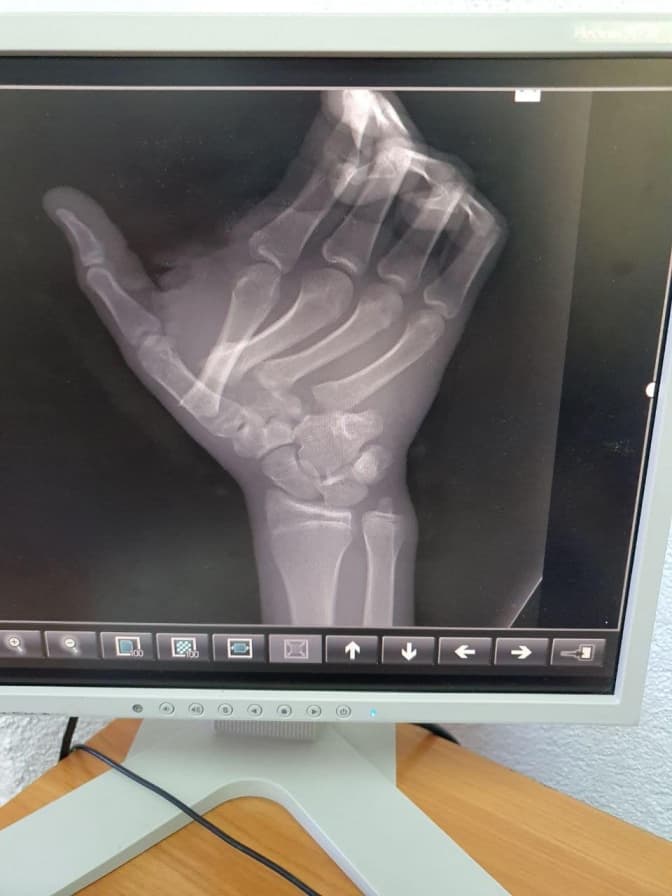

Львівським медикам вдалося зберегли кінцівки хлопця з села Купичволі, що на Червоноградщині, який звернувся до лікарні Св. Миколая зі зміщеними кістками кисті на правій руці та численними нетиповими переломами. Того дня 17-річний Ігор допомагав батькам по господарству, і колесо переїхало йому руку та травмувало кисть.

«Він отримав переломи та вивихи кількох п‘ясних кісток та переломи з відкритими рвано-різаними ранами в ділянці першого та другого пальця. Юнак міг втратити чутливість і здатність рухати кінцівкою, тому його забрали до операційної. Якби втручання не провели вчасно, набряк м’яких тканин кисті міг наростати та притискати нерви. Як наслідок – пальці втратили б чутливість і хлопець перестав би ними рухати», – йдеться в повідомленні.

Пацієнтові провели фасціотомію – розрізали сполучну тканину, аби зняти тиск у кінцівці, та зібрали всі кісточки кисті докупи. Кістки пальців травматологи зафіксували чотирма спицями Кіршнера, які пацієнт носить вже близько місяця.

Зараз він проходить реабілітацію, уже може рухати пальцями та навіть самою кистю. Медики очікують, що рухова функція руки відновиться повністю.